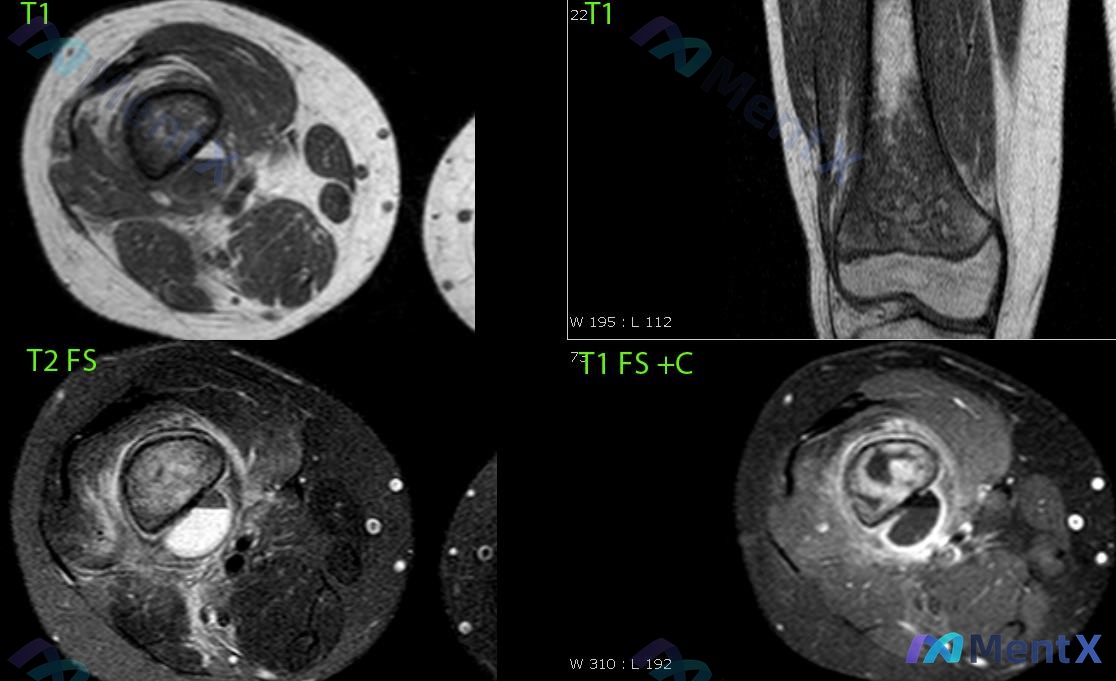

看到一个13岁男性的病例,主诉是膝盖不适,但影像的关键发现却在大腿后侧。整理一下手头的资料和分析思路。 病例基本信息 - 年龄/性别:13岁,男性 - 主诉:膝盖不适 影像核心表现(MRI) 看了四个序列,整理关键阳性和阴性: 1. 病灶位置:大腿中下段后方、股骨与肌肉间隙内,未在膝关节腔内 2....